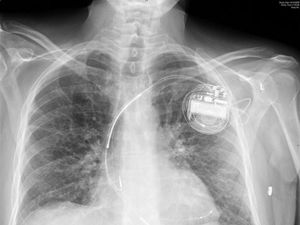

The implanted devices, which regulate heart rhythm, have saved countless lives but suffer from one serious drawback: they run on batteries.